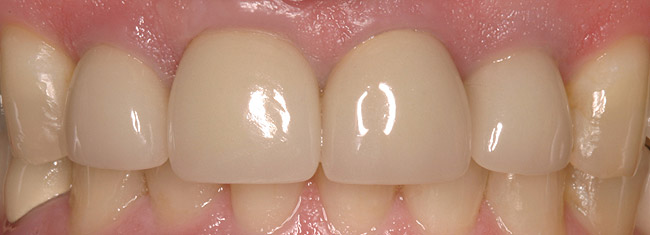

Figure 6d Completed treatment: revised RCT, zirconium post/pressed ceramic core cemented with Panavia 21¬Æ Resin Cement (Kuraray Dental). All-ceramic full-coverage crown cemented with Kerr NX3 Nexus¬Æ Third Generation Dual Cure Resin cement. Implant therapy not indicated.

Figure 6d

Figure 6e  Completed treatment: revised RCT, zirconium post/pressed ceramic core cemented with Panavia 21¬Æ Resin Cement (Kuraray Dental). All-ceramic full-coverage crown cemented with Kerr NX3 Nexus¬Æ Third Generation Dual Cure Resin cement. Implant therapy not indicated.

Figure 6e

Figure 6f  Completed treatment: revised RCT, zirconium post/pressed ceramic core cemented with Panavia 21¬Æ Resin Cement (Kuraray Dental). All-ceramic full-coverage crown cemented with Kerr NX3 Nexus¬Æ Third Generation Dual Cure Resin cement. Implant therapy not indicated.

Figure 6f